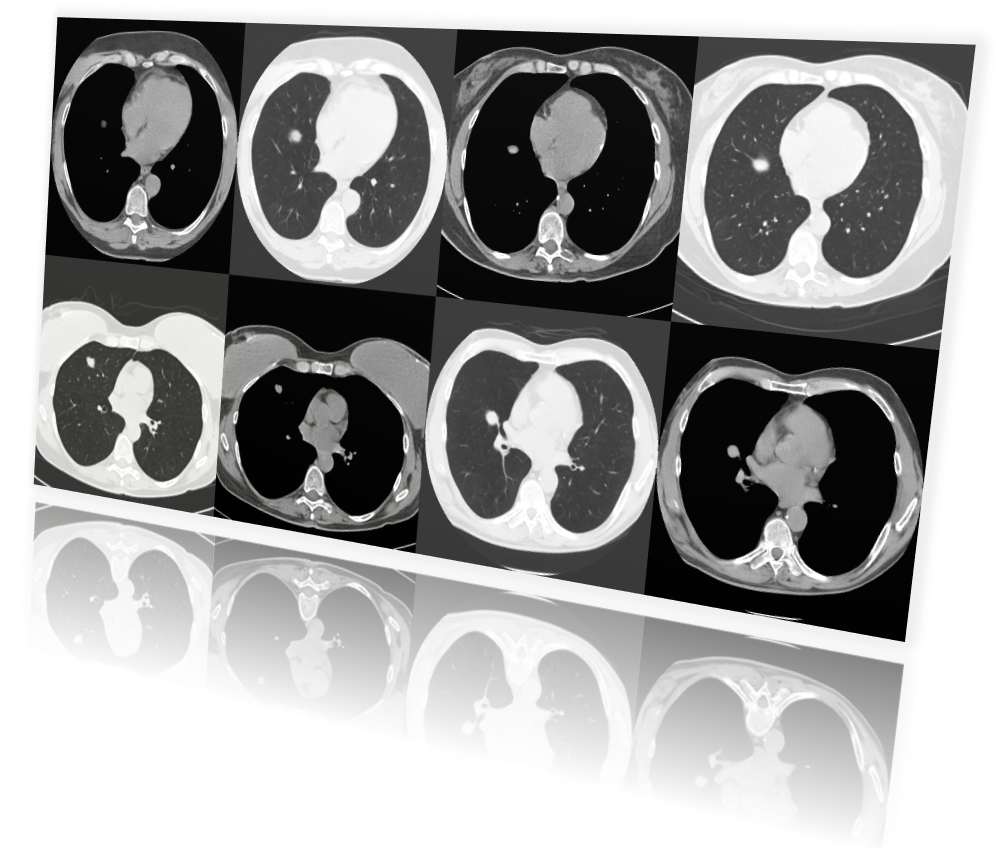

12Bit AI provides you with the tools to generate medical image datasets based on your needs.

We challenged radiologists to see if they could tell synthetically generated radiology images by 12Bit AI apart from real images. The results indicate that radiologists did no better than a coin toss, meaning that their accuracy was only around 50% at identifying real images.